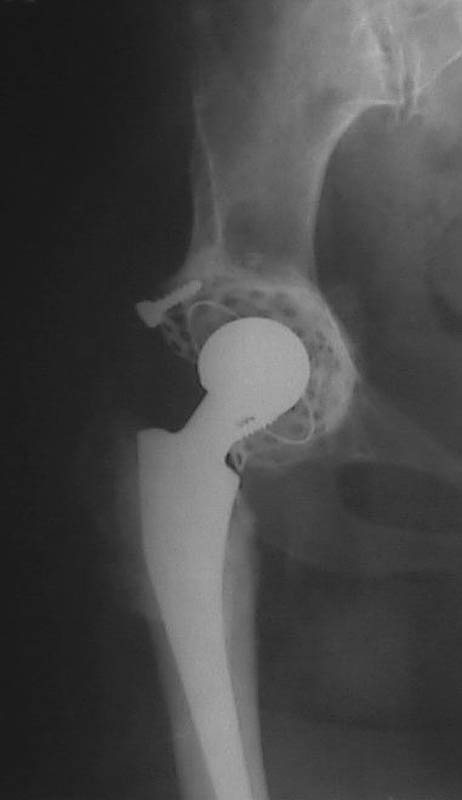

Мужчина, 38 лет. Двусторонний диспластический коксартрз, кифосколиоз.Правый сустав прооперирован 12.12.00, левый - в апреле 2003 г. Справа вывихнулась <чашка>.

Предполагается заменить <чашку>, наростив крышу <тутопластом>? Возможно ли использовать бесцементную <чашку>? Мнения? Заранее благодарю! С уважением,А.В.Владзимирский

На мой взгляд, оптимальным вариантом может быть использование антипротрузионой сетки и цементной чашки. Пластика крыши с учётом величины дефекта - любым материалом на Ваше усмотрение (ауто-, алло-)

Использовать бесцементную чашку я бы не рискнула.